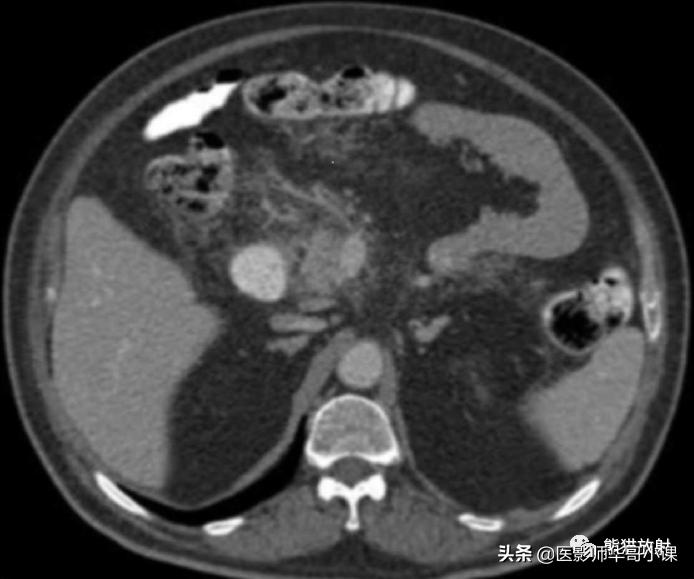

急性胰腺炎时,外渗的胰酶沿肠系膜解剖路径扩散。 胰外急性积液可以沿横结肠系膜根部蔓延 ,有时,也可沿小肠系膜根部蔓延,以及沿血管扩散至横结肠和小肠的直小血管(图)。

急性胰腺炎扩散。增强CT显示炎症从横结肠系膜向横结肠扩散